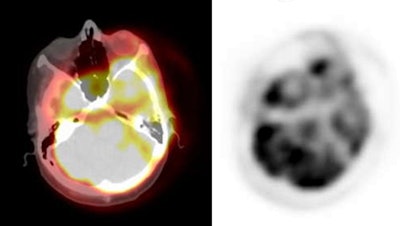

PET/CT exam: The images below are from a PET/CT exam. The patient moved between the acquisition of the CT study and the PET exam- hence- there is misalignment of the two exams. |